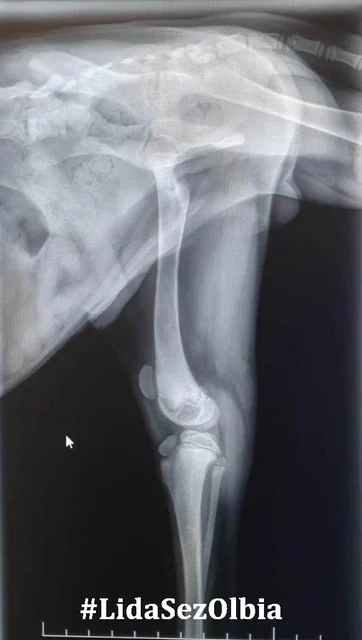

Nach einer Phase der leichten Besserung kamen nun die Beschwerden zurück, aber mit voller Wucht – beide Hinterbeine von Masai versteiften sich durch eine anhaltende Muskelkontraktion.

Blut wurde abgenommen und die Ergebnisse bestätigten den Verdacht:

Neosporose (und Toxoplasmose) positiv.

Die Neosporose der Junghunde ist gekennzeichnet durch progressive, aszendierende Paralyse und Parese der hinteren Extremitäten und ist auch als sogenanntes Neuromuskuläres Syndrom bekannt.

Es hilft hier nur, die betroffenen Extremitäten manuell zu bewegen. Ein sehr schmerzhaftes Prozedere für den Hund, weshalb Masai nun deshalb für die Anwendungen immer sediert wird.

Führen all diese Maßnahmen nicht zum Erfolg, so bleibt nur noch die Amputation der Hintergliedmaßen.